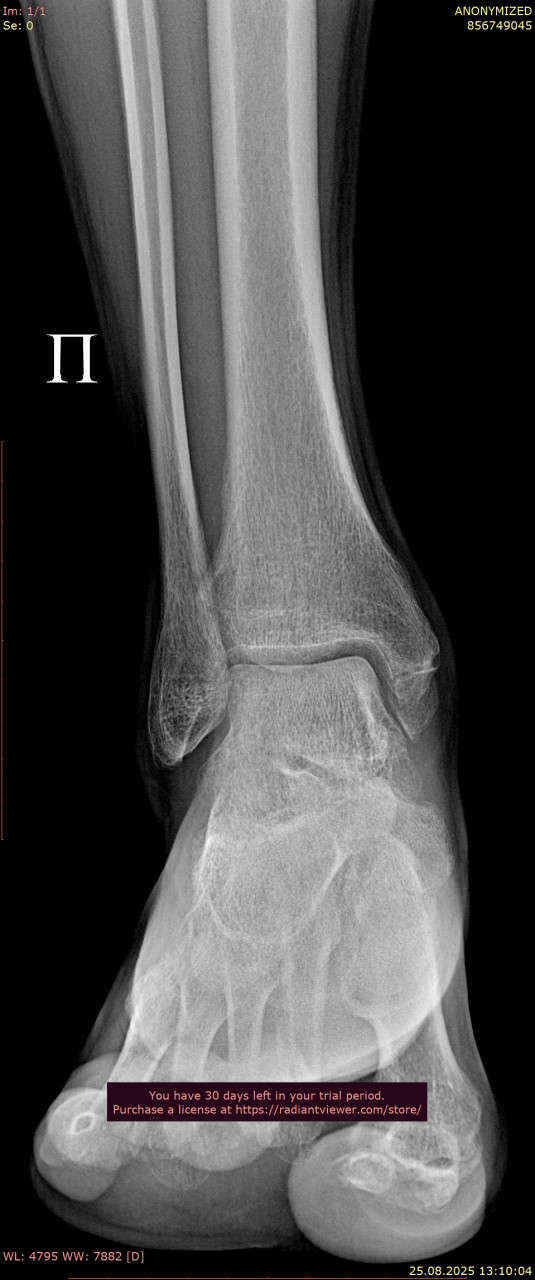

Посмотрите, пожалуйста, еще раз снимки голеностопного сустава, от 23.06.2025, когда был перелом (прикрепляю только 1 проекцию из за лимита файлов на сайте) и от 25.08.2025. Нет ли избыточного разрастания костей в области внутренней лодыжки? Если есть, то какие могут быть последствия? На сегодняшний день боли и ограничения подвижности пока нет. Заранее спасибо!

Здравствуйте. По контрольным снимкам от 25.08 выраженного избыточного костного разрастания в области внутренней лодыжки не видно и отмечается формирование нормального костного мозоля. Если в дальнейшем появятся боли или ограничение движений это может указывать на избыточное разрастание, но сейчас сустав выглядит благополучно. Рекомендую продолжать наблюдение и выполнять ЛФК.